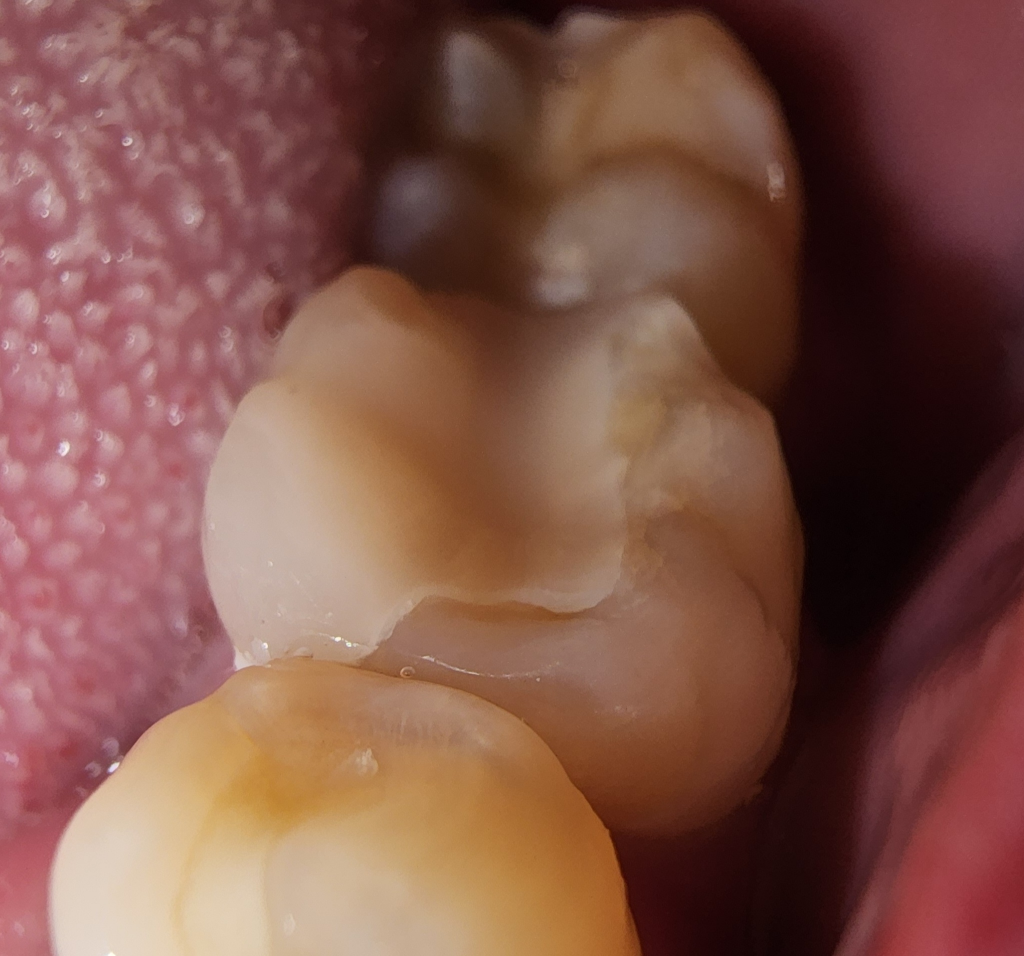

몇일전에 인레이치료 받았는데 마감이...(사진주의)

네이버 인레이한거 사진보면 아주 깔끔하게들 하셨던데. 저는 단차가 있는거 같고 좀지저분한게 된거 같아 문의드려요

이정도면 잘된건가요?

• 2번 째 사진

현재 보여주신 사진은 인레이라기 보다는 온레이에 가깝다고 보시면 됩니다. 즉 단순히 교합면(씹는면)이 아니라 치아의 다른 외형까지 손상되어 한 것으로 보여집니다. 아마 색상 차이로 인하여 훨씬 지금과 같은 생각이 드실 수 있는데 단차가 난다면 다시 해야 하는 것이 맞습니다. 즉 치과 기구로 긁었을 때 자연치와 해당 온레이에 긁히거나 턱이 진다면 다시 제작해야 합니다.

사진상으로 보면 인레이 와 치아공간이잇어 보이긴합니다. 치과에 가셔서 다시한번 체크를 받아보시는게 좋을것같습니다.